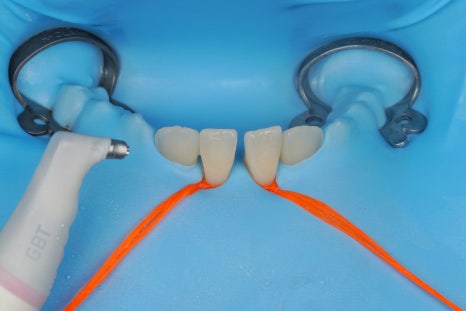

어금니, 앞니 가릴 것 없이

중요한 접착의 순간에

이렇게 러버댐을 사용하는 것,

그래서 구강 내에 있는

뺨과 혀,

피와 침과 습기로부터

치아를 완전히 격리하고 방습하는 것.

그것이 교과서에 적힌 원칙이고

결과를 High-end로 유지할 수 있는

비결입니다.